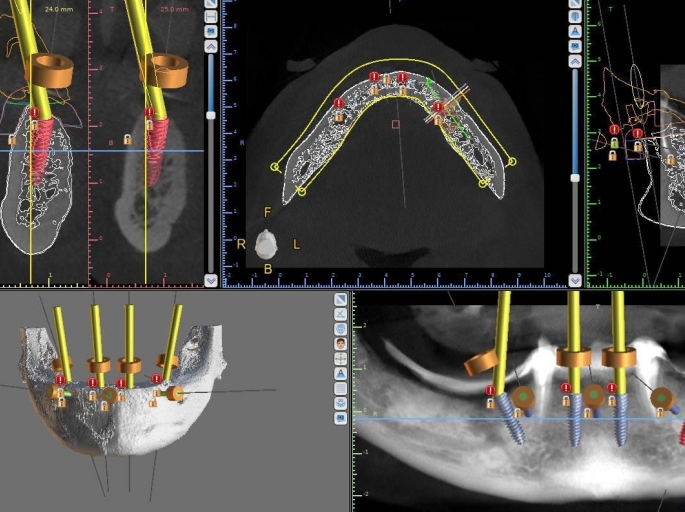

Vă prezentăm un caz All-on-4 finalizat cu succes cu ajutorul a 2 ghiduri chirurgicale realizate 100% cu ajutorul tehnologiei digitale.

Am folosit doua ghiduri: unul pentru osteoplastia crestei alveolare, iar cel de-al doilea pentru inserarea implanturilor.

• precizie în planificare;

• precizie în intervenții chirurgicale;

• precizie în implantarea minim invazivă;

• rezultat perfect predictibil;